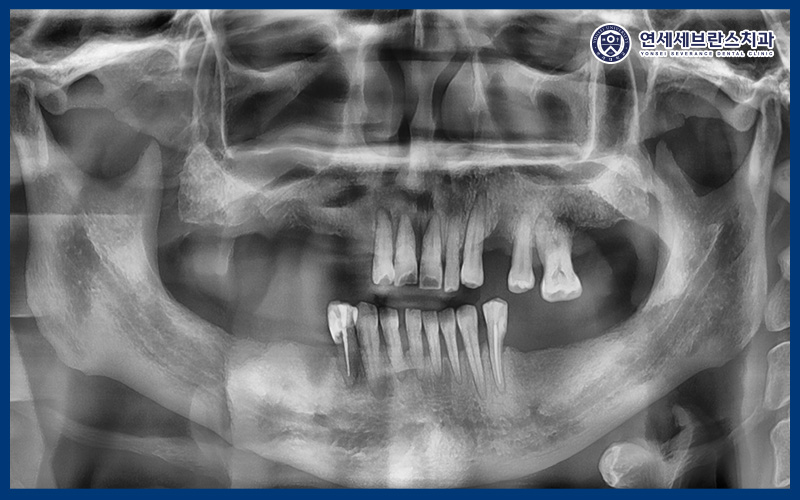

<엑스레이를 통한 정밀한 확인>

확인해 보니,

오른쪽 어금니는 거의 상실되어 있었으며

왼쪽도 아래 치아가 없어

위 치아가 정출되어 있었습니다.

그래서 전체적으로 식사하기도 불편하고

기능이 저하된 상태였으며,

남아 있는 치아에도 과도한 부담이

계속 전달되고 있는 상황이었습니다.

하지만 아래 앞니 같은 경우에는

덜 흔들리는 편이라 치아를 살려 쓰기로 하였으며,

이외의 치아는 전체 발치 후

임플란트를 진행하기로 하였습니다.